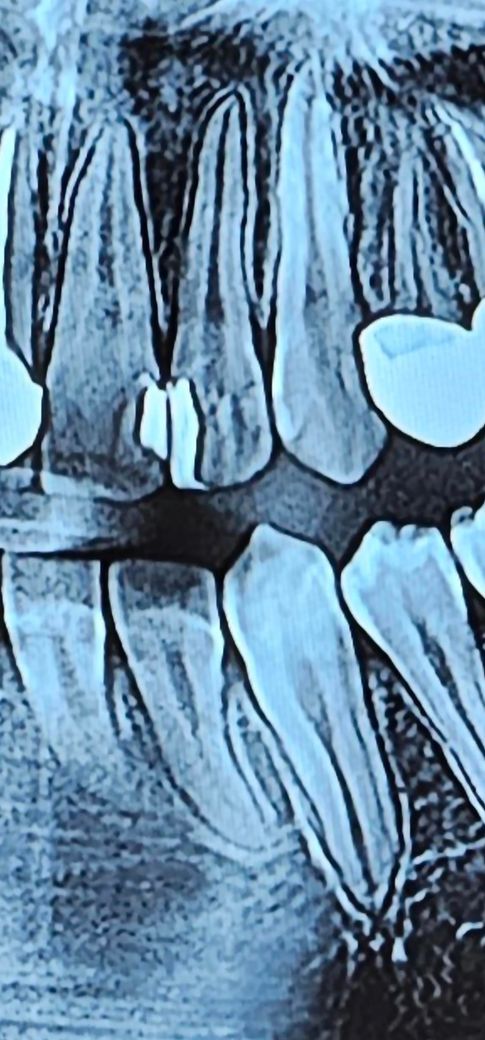

앞니와 옆니 사이가 계속 욱씬거리고 그럽니다 치료한지 1달20일 지났고요 하 씨발 진짜 좆같애서 시간이안돼서 일요일에 여는 마트 치과를 가서 레진치료 받았는데 이를 씨발 개좆으로 쳐 만든거 같습니다 다른 치과에서 한 레진치료는 멀쩡한테 마트에서 한 개 병신같은 저 자신을 원망하고 싶고요 고소와 레진 다 지우고 레진치료에 쓴 비용이 환불되는지 궁금합니다

치료가 잘 된건 맞는지도 알려주세요

그리고 애초에 신경과 가까이 레진을 하기도 하나요?

1. 위 엑스레이 사진만으로는 정확한 평가는 어렵습니다.

2. 신경과 가깝다의 기준은 치과의사마다 조금씩 다를 수 있습니다. 보통 0.5~1mm 정도까지 신경에 근접하면 신경치료 가능성을 환자에게 고지하고, 신경을 보호하기 위한 재료를 깔고 레진을 시도합니다.